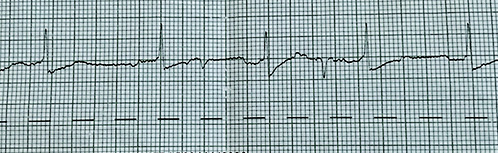

Förmaksflimmer med normal kammarfrekvens.

Förmaksflimmer med snabb kammarfrekvens.